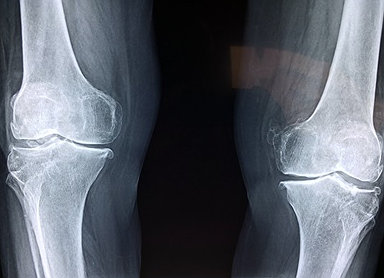

종근당 이모튼 캡슐의 효능은 크게 두가지가 있습니다. 퇴행성 관절염을 포함한 골관절염에 효과가 있습니다. 그리고 치주질환에도 도움이 됩니다. 치주질환으로 발생한 출혈과 통증을 제어하기 위한 보조적인 요법으로 활용될 수 있습니다. 그렇다면 종근당 이모튼 캡슐은 어떻게 복용해야 안전할까요? 다음을 참고하세요.